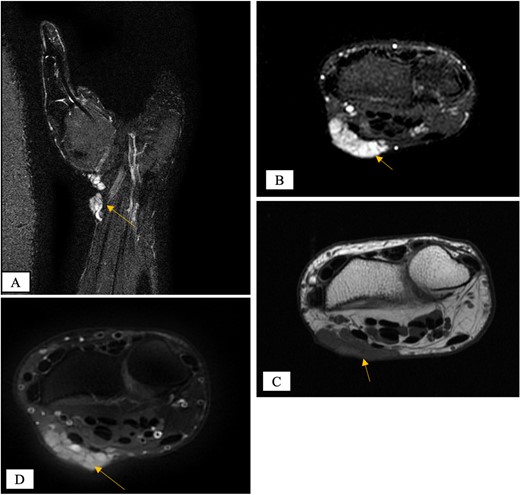

X-ray showed a well-defined non-aggressive lytic bony lesion of the first metacarpal bone (Fig. 1). Magnetic resonance imaging (MRI) showed a grossly stable skin and subcutaneous multilobulated soft tissue mass located at the palmar aspect of the wrist joint measuring 6 × 2 × 3.3 cm3 in its maximum anteroposterior, transverse and craniocaudal dimensions, respectively (Figs 2 and 3). The lesion showed low and high signals in T1 - and T2-weighted images with homogenous contrast enhancement. The lesion was inseparable from the flexor carpi radialis and palmaris longus tendons without definite invasion or encasement. The lesion was not in continuity, however, with the serpiginous lytic bony lesion noted at the first metacarpal bone exhibiting low T1 and high T2 signals with peripheral enhancement and no cortical destruction or associated soft tissue component (Fig. 4).

MRI of the left distal forearm showing cutaneous and subcutaneous lobulated mass at the volar aspect of high T2 and low T1 signals with diffuse enhancement. (A) Coronal T2-weighted fat saturated image. (B) Axial T2-weighted fat saturated image. (C) Axial T1-weighted image. (D) Axial T1-weighted fat saturated image post gadolinium injection.